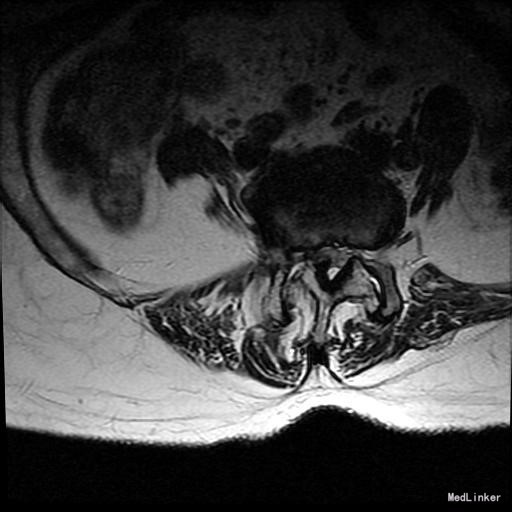

主诉:右下肢麻木11年,腰部酸痛无力 现病史:女性患者,65岁,患者于11年前无明显诱因下出现右下肢麻木,自大腿至右踝部,站立位加重。未予重视,后期出现腰臀部僵硬,弓背僵硬无力,自主行走距离不足200米,曾于06年经X线平片及MRI检查:腰椎椎管狭窄伴有腰椎滑脱,椎间盘突出等。

查体:侧弯畸形,右臀部及右下肢麻木疼痛,腰部活动受限,难以站立。右侧支腿抬高试验60°。双下肢肌力肌张力可。 辅助检查:平片:腰椎侧弯,椎体滑脱,曲度后凸 磁共振:L2-3,L4-5,L5-S1腰椎椎管狭窄,l2-3L3-4L4-5L5-S1腰椎间盘突出,腰椎退变

诊断: 腰椎侧弯,腰椎间盘突出 治疗:1期微创侧路椎体融合术+2期 微创后路经皮内固定术